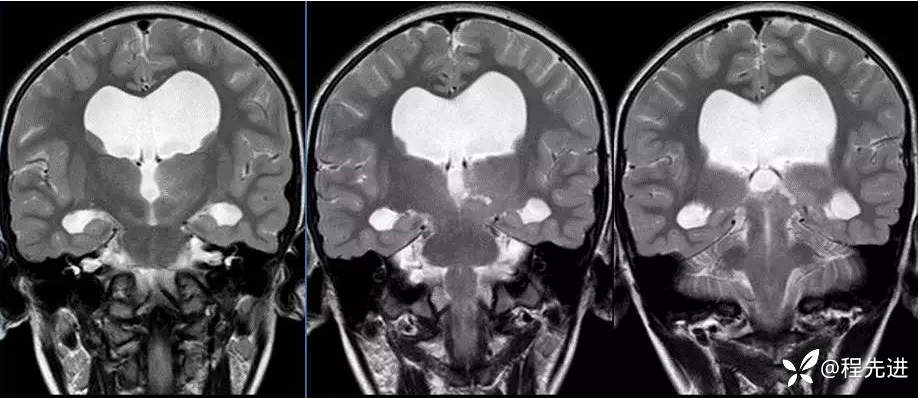

MR